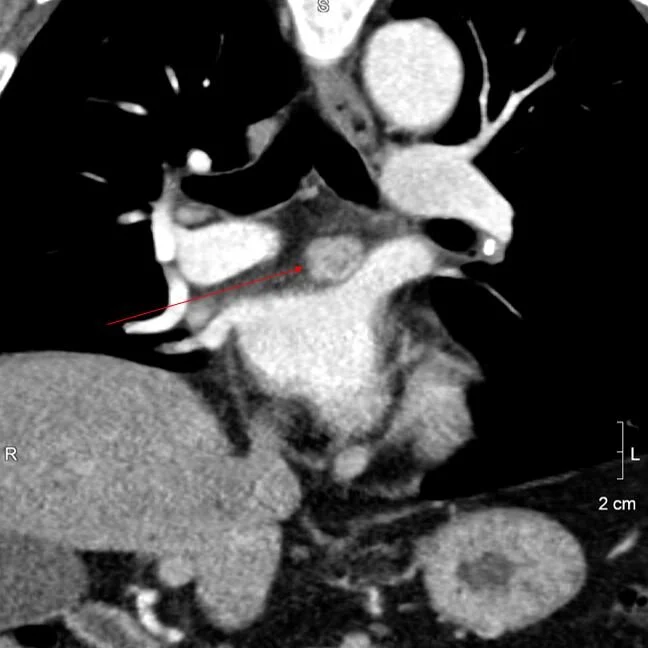

Coronal image shows the nodule is in the roof of the left atrium.